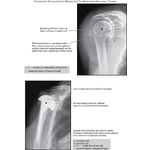

Rotator Cuf-Deficient Arthritis (Rotator Cuff Tear Arthropathy): Radiographic Findings

Rotator Cuff–Deficient Arthritis (Rotator Cuff Tear Arthropathy): Radiographic Findings